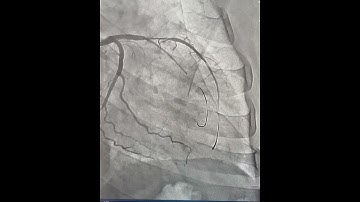

PCI of LAD-D1 and LAD-D2 Bifurcation using Double Mini-Crush Technique